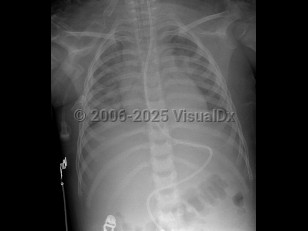

Smoke inhalation in Adult

The most common cause of death in fires is not thermal injury but rather the inhalation of noxious gases. Smoke is made of carbon dioxide, water vapor, carbon monoxide, fine particulate matter, hydrocarbons and other organics, and a variety of other substances. There may be many other toxic substances present in the smoke that increase when certain hazardous materials are burned, such as pressure-treated wood that may contain arsenic or chromate, insulation (including asbestos and fibrous materials), lead paint, particle board, asphalt (in roofing materials), used tires, rubber, plastics, vinyl materials, and foam padding (in mattresses and furniture).

Smoke inhalation can lead to many complications from irritation of the eyes and respiratory tract to acute and chronic lung disorders. The potential health problems will depend on what is being burned, concentrations of toxic substances in the smoke, the length of the exposure, and individual susceptibility (which will vary depending on the health of the individual and any medical problems they may have). The elderly, those with preexisting heart or lung conditions, smokers, and young children may be affected more severely by smoke inhalation.

Carbon monoxide (CO) poisoning frequently results from smoke inhalation. The acute presentation includes headache, dizziness, or nausea. Infants may present with vomiting. In patients with prolonged exposure, coma or seizures can occur, as well as altered mental status, retinal hemorrhages, lactic acidosis, and myonecrosis. Myocardial infarction may occur in the elderly, especially those with heart disease. Cherry-red skin color is associated with CO poisoning (2%-3%).